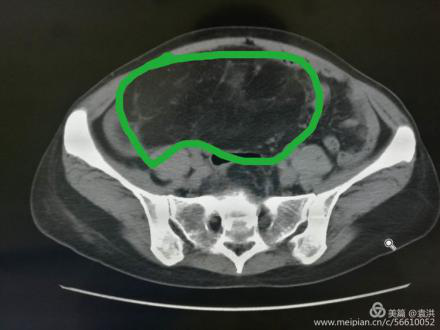

遂請(qǐng)泌尿外科會(huì)診協(xié)助診治,經(jīng)檢查,結(jié)合CT考慮腎周?chē)蚋鼓ず竽[瘤。最終診斷為:右腎巨大脂肪肉瘤。且腫瘤從腹腔延至盆腔,腹腔臟器受壓推移。醫(yī)生建議,子宮肌瘤多為良性,不影響生命,可暫緩手術(shù),但右腎巨大脂肪肉瘤必須盡快手術(shù)摘除。

術(shù)中,可見(jiàn)患者腫瘤包繞右腎,占據(jù)大半個(gè)腹腔,與腹部大血管粘連。經(jīng)過(guò)多學(xué)科聯(lián)合診療(MDT),最終完整切除腫瘤。足足有八斤多重,術(shù)中出血少,無(wú)需輸血。目前患者無(wú)陰道流血不適,待病情穩(wěn)定后,再擇期行子宮肌瘤切除術(shù)。患者丈夫看到這么大的腫瘤,著實(shí)吃了一驚,同時(shí)也感謝醫(yī)生們的妙手仁心。